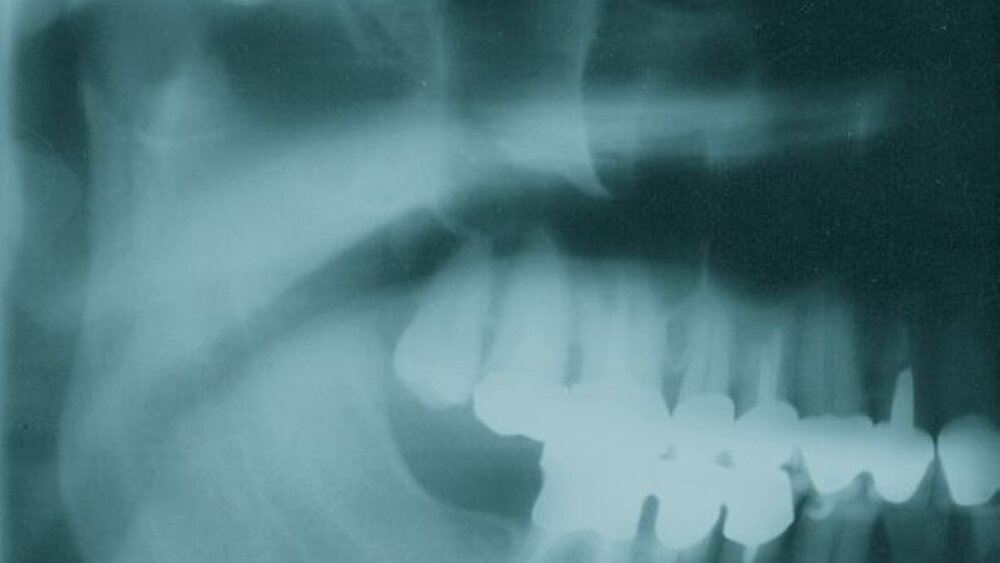

Sowohl das Orthopantomogramm als auch die computertomographischen Aufnahmen zeigten im Bereich des rechten Caput mandibulae eine exostosenartige Struktur, die sich von der normalen Knochenstruktur durch erhöhten Knochengehalt und verminderten Spongiosaraum unterscheidet (Abbildungen 1 bis 3). Sie ist bizarr konfiguriert und hat einen Durchmesser von etwa 15 Millimeter.

Das Vorkommen von Osteomen zentral im Kieferknochen ist selten und tritt erst dann in Erscheinung, wenn Knochenauftreibungen (Exostosen) und Verdrängungserscheinungen im Bereich der Zähne oder auch am Gelenkkopf in Verbindung mit dem Röntgenbefund eindeutige Hinweise liefern [Tochihara et al., 2001]. Im Röntgenbild stellt sich das Osteom als rundlicher, schattendichter Herd mit scharfer Begrenzung dar [Attanasio et al., 1998].